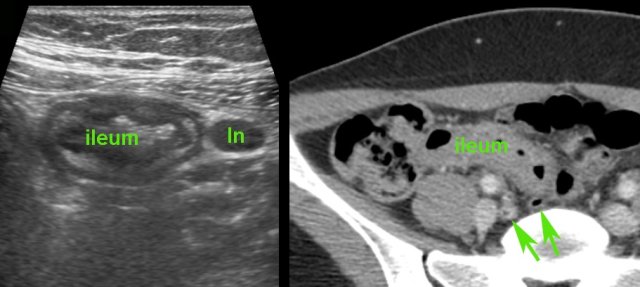

Classic US features of right-sided infectious ileocolitis in a young man.

Prominent mucosal and submucosal wall thickening of terminal ileum and right colon, enlarged inflamed mesenteric lymph nodes and a normal appendix.

Note the prominent ileocecal valve, due to both wall thickening of ileum and cecum in this patient with right-sided Campylobacter ileocolitis.

Right-sided infectious ileocolitis in a 33-year old man.

CT scan without contrast (history of severe allergy).

Prominent (sub)mucosal wall thickening of ileum and right colon.

Note also markedly enlarged mesenteric lymph nodes and normal appendix.